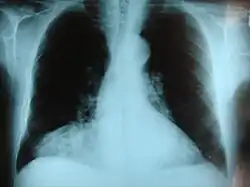

Morgagni hernia seen on a chest radiograph. | |

This rare anterior defect of the diaphragm is variably referred to as a Morgagni, retrosternal, or parasternal hernia. Accounting for approximately 2% of all CDH cases, it is characterized by herniation through the foramina of Morgagni which are located immediately adjacent and posterior to the xiphoid process of the sternum.[4]